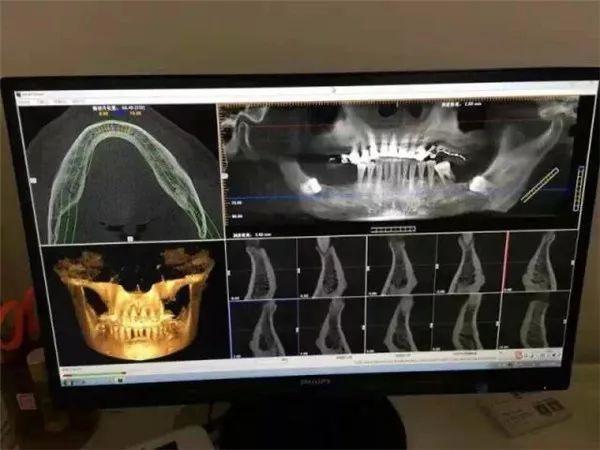

這臺堪稱口腔界“愛馬仕”的德國卡瓦CT機

進一步提升整體診療水平

全新的三維影像系統(tǒng),360度旋轉(zhuǎn)閱片模式

高清晰3D影像圖片質(zhì)量為你提高

更清晰直觀,更準確,更,更的診斷

讓不是醫(yī)生的你也能看懂專業(yè)的影像

1、拍攝CT

經(jīng)過一系列的基礎(chǔ)檢查

蘇志丹的身體狀況適合進行種植手術(shù)

但是具體要用什么樣的種植方案

還需要經(jīng)過這臺德國卡瓦CT機

的“火眼金睛”仔細查看

只需要安靜地坐著

機器會通過對患者360°旋轉(zhuǎn)掃描

獲得三維圖像

“第一次體驗這臺德國卡瓦CT機,感覺很神奇,機器自己的旋轉(zhuǎn),就可以把我口腔情況一覽無遺。”

電腦同步得到卡瓦機掃描的數(shù)據(jù)

利用德國卡瓦CT機判斷

全口牙床的位置、牙槽骨的高度和深度等

醫(yī)生可在計算機上清楚判讀出牙槽骨的情況

重建成3D數(shù)字模型